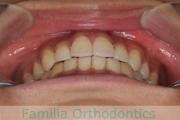

でこぼこと口元が出ている横顔が気になるとのことで来院されました。重度の叢生(ガタガタ)と側方へのズレがあるため、アンカースクリューを併用したマルチブラケット法にて治療を行いました。3年弱、35回程度の通院をしていただきました。叢生が強いため、部分的にガタガタが再発・後戻りするリスクが高いケースでした。

- ≫治療前

-

上顎

下顎

前歯の関係など

右側

正面

左側

- ≫治療後